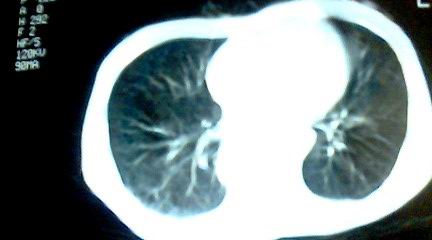

标题: CT25218:请教!胸部CT,胸8椎体骨质破坏,伴周围软组织肿。 [打印本页]

标题: CT25218:请教!胸部CT,胸8椎体骨质破坏,伴周围软组织肿。

患者,女41岁,肢体乏力。

双肺及胸椎结核。

双肺及胸椎结核。支持!

两肺上叶继发性肺结核;胸椎结核并椎旁寒性脓肿形成。

两肺上叶继发性肺结核;胸椎结核并椎旁寒性脓肿形成